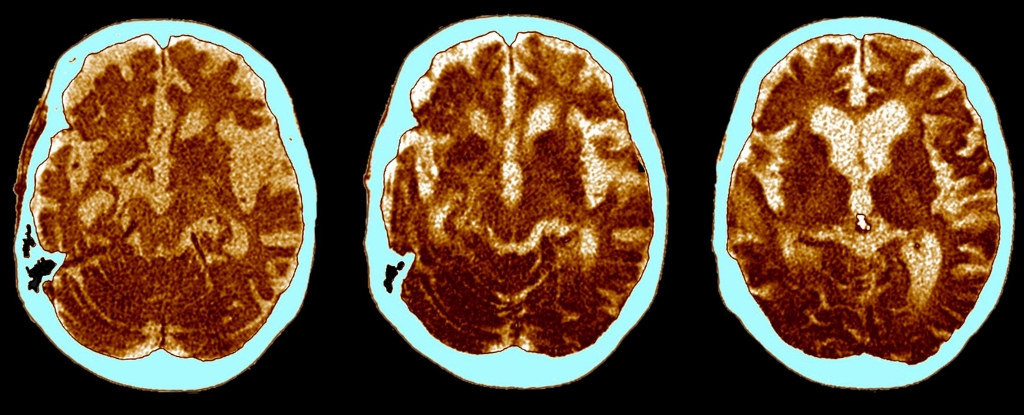

A Regular Vaccine Could Reduce the Risk of Dementia by Up to 20%

For the last two hundred years, vaccines have played a vital role in preventing infectious diseases. The World Health Organization suggests that vaccination saves around 3 million to 5 million lives each year from illnesses like diphtheria, tetanus, influenza, measles, and more recently, COVID-19. There’s been a long-standing scientific consensus on vaccines being effective in […]